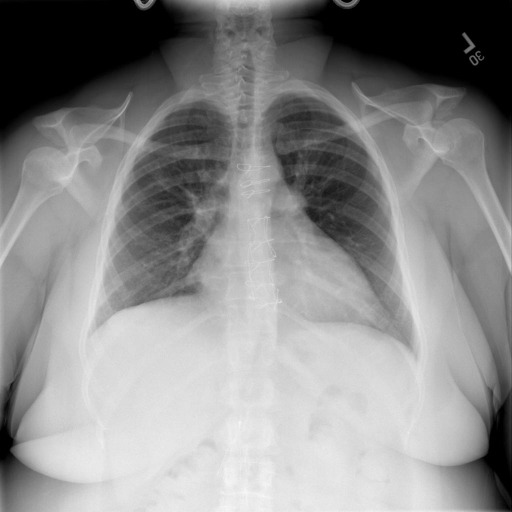

- (1)准备[诊疗报告(中文)](./data/Xray/openi-zh.json)和[X光影像](https://pan.baidu.com/s/13GBsDMKf6xBZBSHpoWH_EA?pwd=k9sh)在`data/Xray`文件夹下; - (2)开始训练: ```bash # 设置CUDA变量,主要是为了解决有时候直接训练而出现无法正确加载到显卡问题 export CUDA_VISIBLE_DEVICES=0,1,2,3 # 开始训练 bash finetune_XrayGLM.sh ``` 这里的复现过程非常简单,主要是很多过程我们都为大家准备好了,大家可以随时复现一个自己的`XrayGLM`。 ### 4.模型训练(通用) ## 效果展示 *以下效果来自于**低质量**的数据训练和权重 影像诊断: |X光影像|诊疗报告(医生)|XrayGLM| |:-|:-|:-| |![](./data/Xray/2_1.png)|根据X射线图像,心脏大小正常,肺部看起来很清晰。已经排除了肺炎、积液、水肿、气胸、腺病、结节或肿块的存在。该发现表明一切正常。换句话说,总体印象是胸部正常。|X光片显示,心脏大小正常。肺部没有气胸或胸腔积液的证据。骨骼结构看起来没有任何异常。总的来说,X光片表明没有发现急性心肺疾病的迹象。| |![](./data/Xray/2882_1.png)|X光图片显示没有扭曲的区域、可疑的骨质不透明度或胸腺积液。心脏大小轻微增大,但非常稳定。此外,没有气胸的证据,肺野也正常。总体来说,X光片显示没有急性心脏异常,但要注意轻微的心脏扩大。|X光片显示,心脏大小正常。肺部和纵隔轮廓清晰,没有气胸或胸腔积液的证据。骨骼结构完整,没有任何急性异常。| |![](./data/Xray/2577_1.png)|心影形态在正常范围内。没有急性骨质异常。有可能出现没有明显的吸水或肺实质状况的线索。没有大面积积液或气胸。有可能怀疑其有误吸或肺实质问题。为了确诊和治疗,可能需要进行适当的影像学随访。|心脏大小正常,肺部和纵隔轮廓清晰。没有急性异常或活动受限的证据。没有任何明显的气胸、胸腔积液或肺不张的迹象。此外,也没有发现任何局灶性骨质异常或其他急性疾病。| 多轮对话: |X光影像|诊疗报告(医生)| |:-|:-| |![](./data/Xray/861_1.png)|右侧主动脉突出观察到。心脏大小正常。胸部未发现明显的肺气肿、胸膜积液或可疑的肺部病变。报告指出已知右侧主动脉情况正常。| ```bash >> X光影像路径:./data/Xray/861_1.png >> 用户:这是一张什么图? >> XrayGLM:这张图片显示的是一张肺部检查的X光片。 >> 用户:请描述这张胸部X光片的诊断结果 >> XrayGLM:心脏大小正常,肺部清晰。没有急性心肺疾病的证据。 >> 用户:是否存在肺气肿? >> XrayGLM:没有肺气肿。心脏大小正常,肺部清晰。没有发现急性心肺疾病的证据。 >> 用户:平时饮食该注意什么? >> XrayGLM:饮食应该健康,均衡。建议增加蛋白质的摄入量,因为蛋白质有助于维持肌肉和骨骼的健康。多食用蔬菜、水果、全谷物以及健康的脂肪来源如橄榄油、鱼类等可以帮助获得足够的维生素和矿物质。此外,避免过度饮酒或吸烟,这些习惯可能会对心脏健康产生负面影响。 ``` ## 未来展望 1. 模型的能力更多来源于数据的支持,`OpenI-zh`作为微调数据集,其数据量足以支持研究,在更广泛的任务和性能表现上,我们认为**在大规模数据集上预训练并在高质量少量数据集上微调是一种可行的方案**; 2. 普遍意义的理解上,视觉多模态模型=视觉模型+语言模型。除了需要关注视觉模型信息与语言模型输出的搭配外,还需要**额外关注到语言模型的加强,在人机的对话中,尤其是医疗语言模型的问答上,除了专业的医疗问题回答,带有人文情怀的有温度的回答更应该是我们追寻的目标**。 ## 项目致谢 1. [VisualGLM-6B](https://github.com/THUDM/VisualGLM-6B)为我们提供了基础的代码参考和实现; 2. [MiniGPT-4](https://github.com/Vision-CAIR/MiniGPT-4)为我们这个项目提供了研发思路; 3. ChatGPT生成了高质量的中文版X光检查报告以支持XrayGLM训练; 4. [gpt_academic](https://github.com/binary-husky/gpt_academic)为文档翻译提供了多线程加速; 5. [MedCLIP](https://github.com/RyanWangZf/MedCLIP) 、[BLIP2](https://huggingface.co/docs/transformers/main/model_doc/blip-2) 、[XrayGPT](https://github.com/mbzuai-oryx/XrayGPT) 等工作也有重大的参考意义; ![](./assets/images/mpu.png) 这项工作由[澳门理工大学应用科学学院](https://www.mpu.edu.mo/esca/zh/index.php)硕士生[王荣胜](https://github.com/WangRongsheng) 、[段耀菲](https://github.com/IsBaSO4) 、[李俊蓉](https://github.com/lijunrong0815)完成,指导老师为檀韬副教授、[彭祥佑](http://www.patrickpang.net/)老师。 *特别鸣谢:[USTC-PhD Yongle Luo](https://github.com/kaixindelele) 提供了有3000美金的OpenAI账号,帮助我们完成大量的X光报告翻译工作 ## 免责声明 本项目相关资源仅供学术研究之用,严禁用于商业用途。使用涉及第三方代码的部分时,请严格遵循相应的开源协议。模型生成的内容受模型计算、随机性和量化精度损失等因素影响,本项目无法对其准确性作出保证。即使本项目模型输出符合医学事实,也不能被用作实际医学诊断的依据。对于模型输出的任何内容,本项目不承担任何法律责任,亦不对因使用相关资源和输出结果而可能产生的任何损失承担责任。 ## 项目引用 如果你使用了本项目的模型,数据或者代码,请声明引用: ```bash @misc{wang2023XrayGLM, title={XrayGLM: The first Chinese Medical Multimodal Model that Chest Radiographs Summarization}, author={Rongsheng Wang, Yaofei Duan, Junrong Li, Patrick Pang and Tao Tan}, year={2023}, publisher = {GitHub}, journal = {GitHub repository}, howpublished = {\url{https://github.com/WangRongsheng/XrayGLM}}, } ``` ## 使用许可 此存储库遵循[CC BY-NC-SA](https://creativecommons.org/licenses/by-nc-sa/4.0/) ,请参阅许可条款。